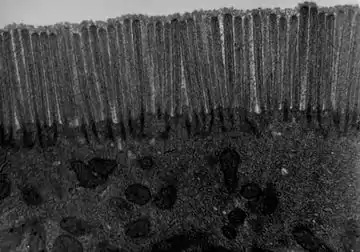

TEM image of mouse jejunum (14,000-fold magnification)

The interior surface of the jejunum—which is exposed to ingested food—is covered in finger–like projections of mucosa, called villi, which increase the surface area of tissue available to absorb nutrients from ingested foodstuffs. The epithelial cells which line these villi have microvilli. The transport of nutrients across epithelial cells through the jejunum and ileum includes the passive transport of sugar fructose and the active transport of amino acids, small peptides, vitamins, and most glucose. The villi in the jejunum are much longer than in the duodenum or ileum.

- The villi of the jejunum look like long, finger-like projections, and are a histologically identifiable structure.